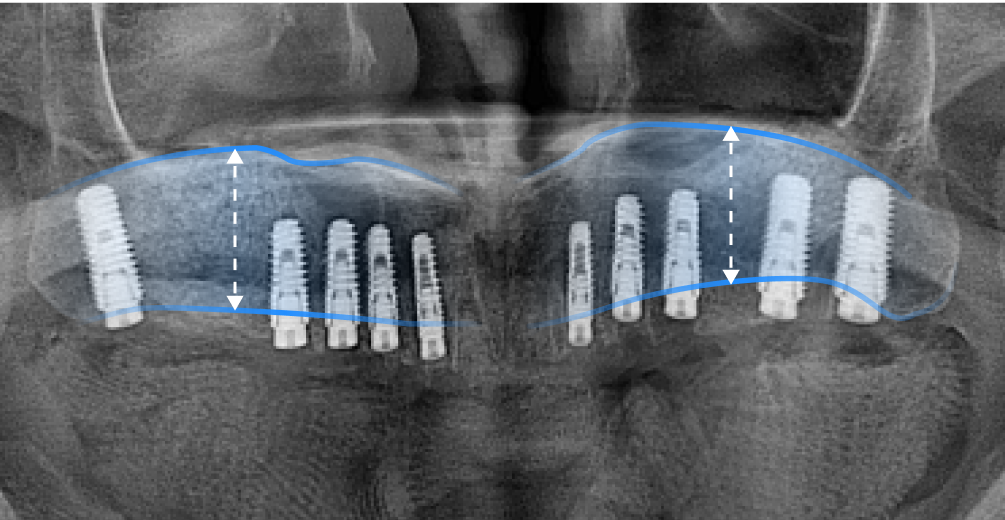

상악동(위턱뼈 속의 비어있는 공간)거상술은 상악동과 잇몸뼈 사이에 임플란트를 심을 수 있는 만큼의 충분한 뼈가 존재하지 않을 때, 그 공간을 살짝 들어 올려서 잇몸뼈를 채워 넣는 시술 을 말합니다.

상악동은 원래 팽창하려는 성질이 있어 치아가 빠진 이후 오랜 시간 방치했거나 나이가 들면서 치조골이 약해지면 상악동이 아래로 내려오면서 커지는 증상이 발생합니다. 이를 상악동의 함기화(Sinus Pneumatization) 라고 하며, 상악동이 아래로 내려오면서 임플란트 식립이 어려울 만큼 뼈가 얇아지게 됩니다. 이렇게 뼈가 얇아져 임플란트 식립이 어려울 때, 상악동을 위로 들어 올려 뼈를 이식하는 ‘상악동 거상술(Sinus Lift , Sinus Elevation)’을 진행합니다.

• 상악동 거상술 전

상악동 거상술 전, 얇은 잇몸뼈

• 상악동 거상술 후

상악동 거상술 후, 두꺼워진 잇몸뼈

*노란선 : 잇몸뼈와 상악동의 경계선 *파란선 : 상악동 거상술 이후 잇몸뼈와 상악동의 경계선